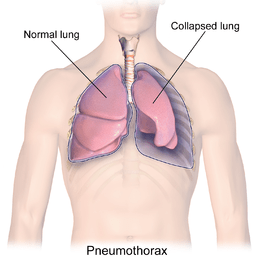

This Problem basically from the Healthcare domain. imagine suddenly

gasping for air, helplessly breathless for no apparent reason. Could it be a

collapsed lung? In the future, we are going to predict this answer.

Pneumothorax can be caused by chest injury, damage from underlying

lung disease, or most horrifying — it may occur for no obvious reason at all.

On some occasions, a collapsed lung can be a life-threatening event.

Pneumothorax is usually diagnosed by a radiologist on a chest x-ray

images ,but sometimes it could be difficult to confirm.

Pneumothorax is visually diagnosed by radiologist, and even for a

professional with years of experience; it is difficult to confirm.

So Our Goal is to Detect and Segment those Pneumothorax affected area with a help of Semantic Segmentation methods,so that we can help the radiologist by giving the results with higher precision.